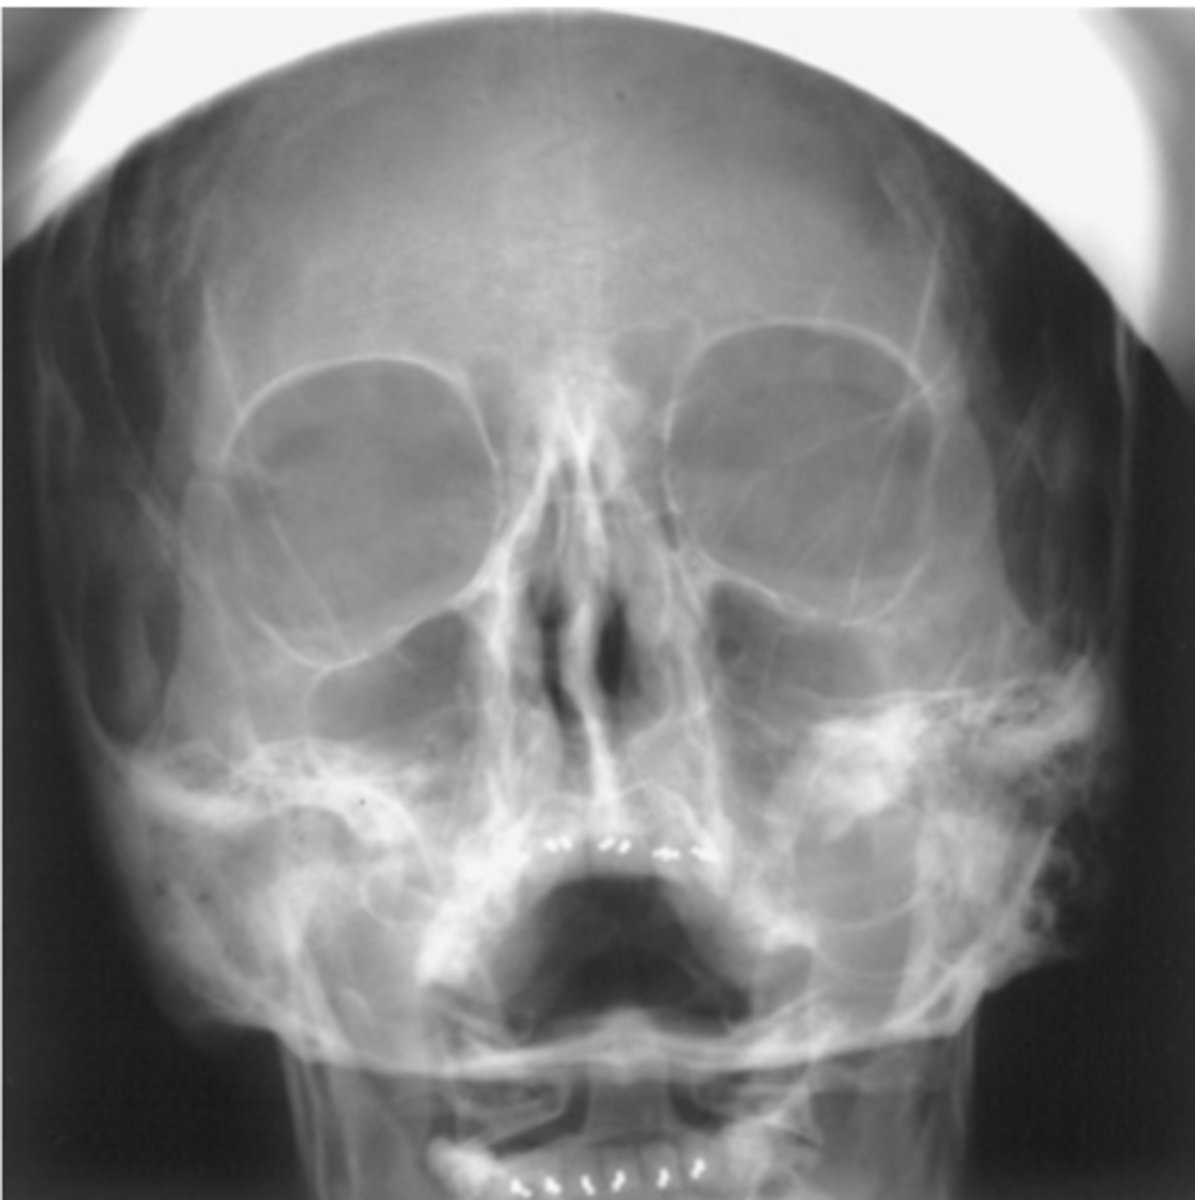

Critique parietoacanthial (Waters) projection.

Repeatable errors (three)—

Criterion 1: Anatomy demonstrated: Maxillary sinuses are not well demonstrated. Petrous ridges are projected into the lower aspect of maxillary sinuses. Artifacts appear to be both surgical clips and devices (acceptable) and external hair pins and clips (not acceptable).

Criterion 2: Positioning: The skull is underextended and severely rotated. This results in projection of petrous ridges into the lower aspect of the maxillary sinuses. Artifacts appear to be external hair pins or clips

Criterion 5: Anatomic side markers: No anatomic side marker is visible.